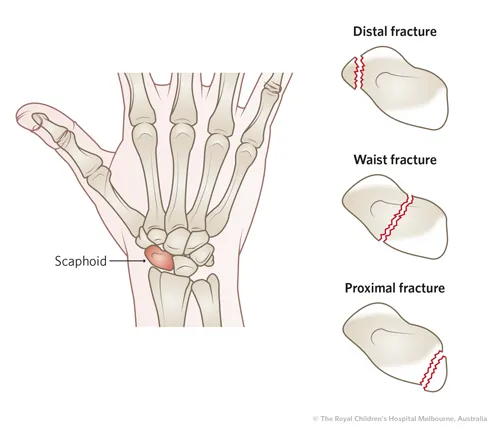

Een scaphoid non-union betekent dat een gebroken scaphoid (ook wel scheepsvormig handwortelbeentje genoemd) niet is vastgegroeid. Het scaphoid is een klein botje aan de duimzijde van de pols dat vaak breekt bij een val op de hand. Normaal hoort zo’n breuk binnen 6-8 weken te genezen. Bij een scaphoid non-union gebeurt dit niet: de twee botstukken van het scaphoid groeien niet meer aan elkaar, waardoor een blijvende breuklijn (pseudartrose) in het bot ontstaat. Dit kan komen doordat de breuk gemist of onvoldoende behandeld werd, of door slechte doorbloeding van het gebroken deel (met name bij een breuk in het proximale deel, dichtst bij de onderarm, van het scaphoid is de bloedvoorziening beperkt). Het resultaat is een instabiel polsgewricht dat na verloop van tijd kan leiden tot slijtage (artrose) in de pols.

- Slechte doorbloeding: Bij sommige scaphoidfracturen, vooral aan de kant dicht bij de onderarm (proximale pool), is de bloedtoevoer naar het fragment minder goed. Dit deel van het bot krijgt onvoldoende voedingsstoffen om te genezen, wat kan leiden tot een scaphoid non-union ondanks adequate behandeling.

- Bottransplantaat (bone graft): Om de opening tussen de twee stukken scaphoid op te vullen en genezing te stimuleren, plaatst de chirurg vers botmateriaal tussen de delen. Dit bot wordt meestal elders uit je eigen lichaam gehaald, bijvoorbeeld uit de rand van het spaakbeen of uit het bekken. Soms gebruikt men een gevasculariseerd bottransplantaat: een stukje bot met een eigen bloedvat eraan, om de doorbloeding te verbeteren, vooral als het proximale deel (dichtst bij de onderam) van het scaphoid dood (necrotisch) is.